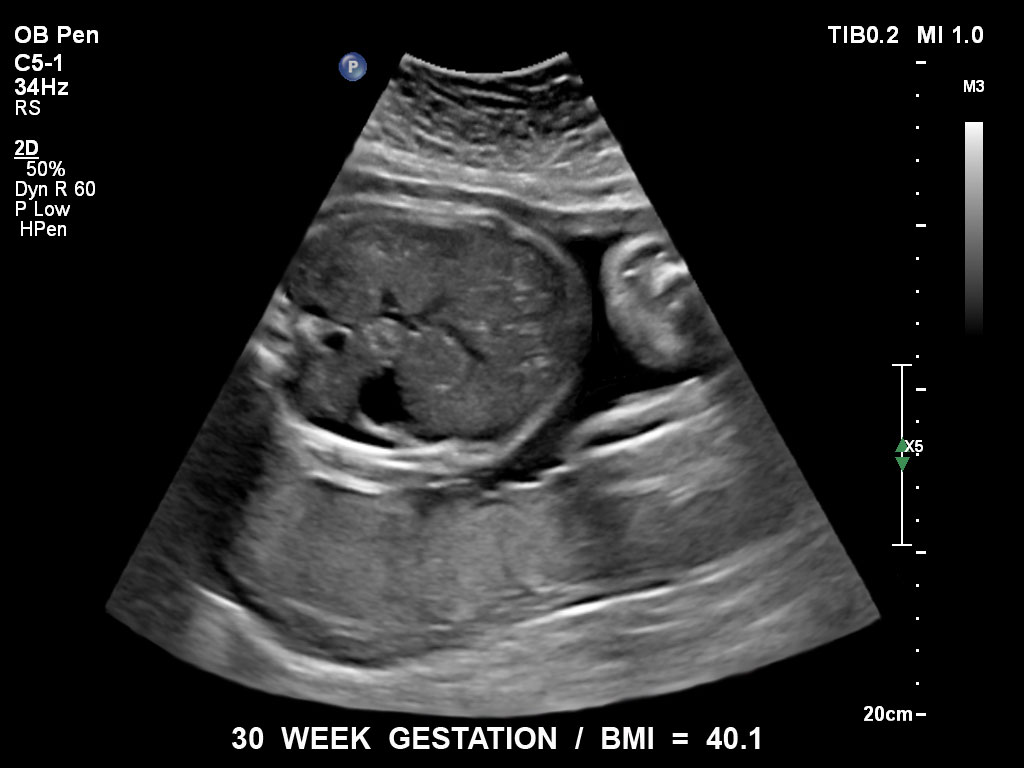

• C5-1 PureWave-Breitband-Convex-Schallkopf für hohe Eindringtiefen in der Gynäkologie und der Geburtshilfe, für Patientinnen mit Schwangerschaftsdiabetes oder vorzeitigem Blasensprung